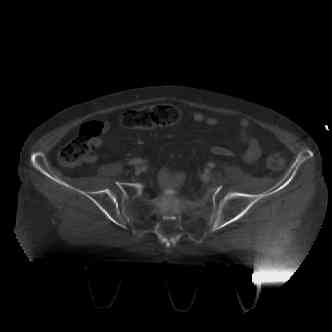

attached are several CT cuts. please let me know if you need more. the CT is pre-pelvic ex-fix placement.

Thank you.

injuries are limited to the pelvis. left rami open and visible in a 10cm vertical laceration just lateral to left labia majora. wound is grossly clean. no vaginal and no urinary issues. CT scan shows widening of both SI joints anteriorly but I think this is vertically stable pattern.

so the question is what next operatively if anything? concerns are infection, nonunion anteriorly and possible incompetence of the pelvic floor which may lead to prolapse issues. right rami are comminuted and plating may entail ilioinguinal approach to extend plate laterally to right iliac wing. retrograde screw up right rami is an option but I am not convinced it will add much. adding SI screws very doable, but major concern is restoring anterior ring. so far wound is clean and closed over a drain, and I have no plans to open it back up and wash again.